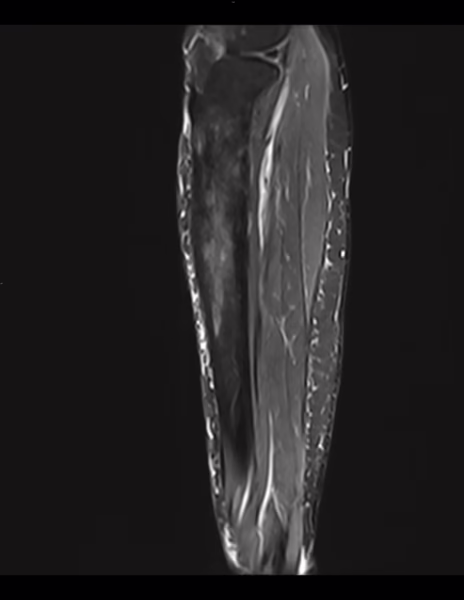

rnm

Se realizaron cortes sagitales, axiales y coronales con técnica de espín eco con el protocolo habitual.

Se identifican edema en el tejido celular subcutáneo adyacente a la tibia y grupos musculares en la región anterior y medial de la pierna.

Existen cambios en la morfología e intensidad del hueso esponjoso de la tibia que involucra la diáfisis proximal y tercio medio con áreas de baja intensidad en el hueso esponjoso medular así como de mayor intensidad, la cortical al parecer se encuentra conservada.

La intensidad de las estructuras musculares se encuentra conservada.

IMPRESION DIAGNOSTICA:

Edema en el tejido celular subcutáneo adyacente a la tibia y grupos musculares en la región anterior y medial de la pierna.

Existen cambios en la morfología e intensidad del hueso esponjoso de la tibia que involucra la diáfisis proximal y tercio medio con áreas de baja intensidad en el hueso esponjoso medular así como de mayor intensidad, la cortical al parecer se encuentra conservada, cambios de proceso infiltrativo óseo de etiología a determinar.